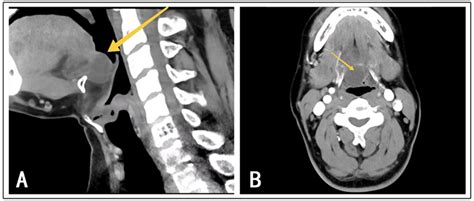

Diagnosis of Cyst Thyroglossal Duct

The diagnosis of a Cyst Thyroglossal Duct typically involves a combination of physical examination and imaging studies. The healthcare provider will perform a thorough physical examination to assess the size, location, and characteristics of the cyst. Imaging studies, such as ultrasound, computed tomography (CT) scan, or magnetic resonance imaging (MRI), may be ordered to confirm the diagnosis and rule out other potential causes of the neck mass.